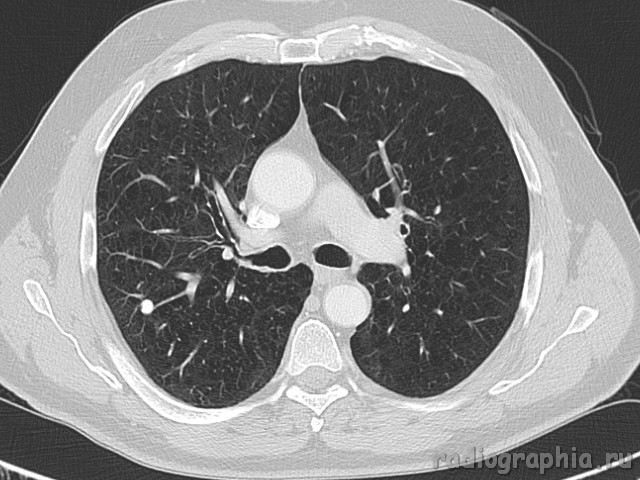

Одиночный узел правого лёгкого.

На рутинном снимке ОГК, был выявлен одиночный узел; по протоколу выполнили КТ. Какое было бы ваше заключение; и как бы Вы поступили если у вас нет возможности выполнять КТ?